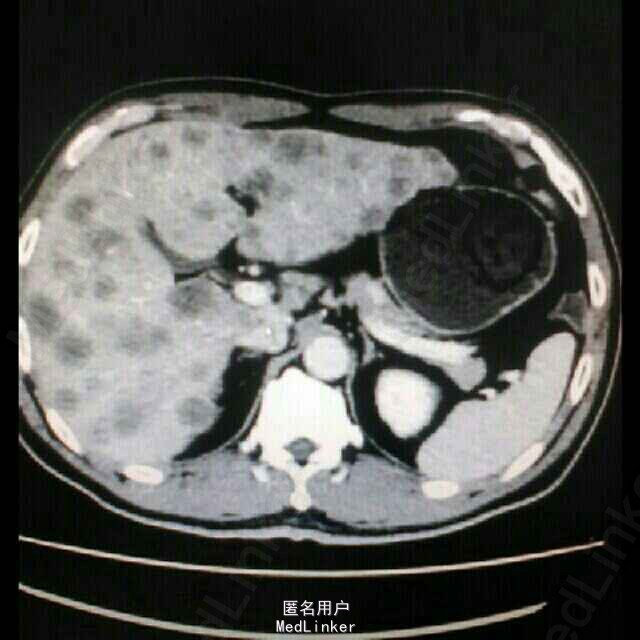

入院后查全腹部CT示:回盲部升结肠癌,累及浆膜层,周围多发肿大淋巴结,肝多发转移瘤(相当壮观,亲们点开图感受一下),肠镜下升结肠肿物活检病理示:中~低分化腺癌,Ki-6780%+.

考虑诊断“结肠癌肝多发转移”,与送检RAS基因,回报示:RAS基因突变野生型。遂予爱必妥(西妥昔单抗)+FOLFOX方案化疗7程。4程后复查胸腹部CT提示肿瘤明显缩小,评价疗效PR(部分缓解)。7程后复查肝内转移瘤增多增大,考虑进展,遂改用安维汀(贝伐单抗)+FOLFIRI方案化疗2程,2程后复查肿瘤标记物升高,且患者腹较前明显,肿瘤有进展趋势,考虑患者靶向药物及化疗疗效短暂,考虑原发耐药可能,且患者一般情况较前变差,KPS评分70分,癌痛明显。